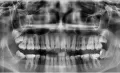

Третий день болит зуб, усиливается боль по ночам и в положении лежа. При накусывании боли нет. При пальпации десен боли нет. Реакция на холодное ― боль усиливается, потом стихает. При этом холодный компресс на щеку со стороны больного зуба боль снижает.

Боль в районе 7 и 8 зуба на нижней челюсти. 7-ка пролечена 6 лет назад, поставлена кальциевая прокладка, зуб не депульпирован. 8-ка имеет кариес. Боль также при пальпации под челюстью чувствуется. При этом боль не острая, а ноющая, тянущая, распирающая. Не стреляет.